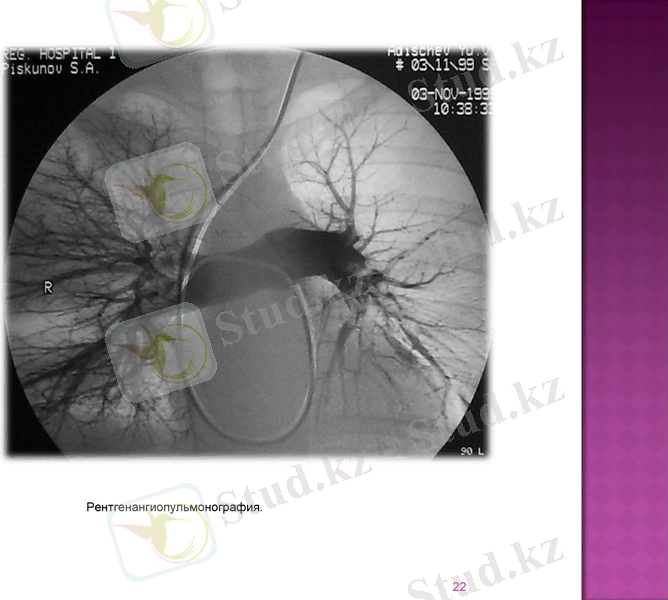

Ангиопульмонография

Схема ангиограммы легких при тромбоэмболии ветви легочной артерии (а) . Стрелкой показан артериальный дефект наполнения в области локализации эмбола и обрыв наполнения артерии («культя» артерии) ; б - нормальная ангиограмма (схема)